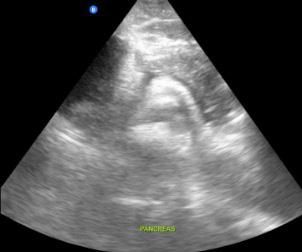

Dr. Artiga’s academic interests include ultrasound, education, and advocacy. Within SAEM RAMS, he has led initiatives such as the Ask-A-Chair educational podcast series, advocacy efforts related to unionization, social media campaigns to promote resident engagement, and the development of board review resources for emergency medicine certification. He has recently taught ultrasound to emergency medicine programs in Latin America.

It was an extremely humbling and eye-opening experience. I went to teach in my father’s country, El Salvador, where I had never visited before. I never truly understood the conditions he lived in beyond his words. All the issues that exist in the U.S. are magnified when you go to countries that don’t have similar resources. Medical decision making is limited by access to resources. It’s not about a lack of capability. I worked with incredibly brilliant doctors who just don’t have access to the same technology or infrastructure we have here. That’s why I believe in supporting ultrasound specifically in these settings. In capable hands, point-ofcare ultrasound can give a clinician life-saving information. Providing this tool and empowering physicians to use it can have a huge impact on individual patients and healthcare systems across the world.

For me, it’s been about chasing my passion and asking, “Who’s on this ride with me?” I’ve always been drawn to ultrasound. Through SAEM’s and the Academy for Emergency Ultrasound’s (AEUS’s) ultrasound didactics and activities, I’ve noticed similar faces showing up. These spaces allow for ideas to connect and develop in ways that don’t happen when you're working alone. You can’t have synergy in isolation. You need people who challenge and inspire you to promote growth. It’s individuals working together, learning from one another, and pushing ideas forward that produce progress.